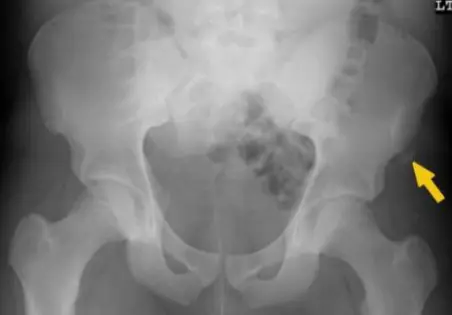

A teenager with acute onset of pain in the right hip during a run. He sustained the injury seen in the x-rays with a white arrow. This injury usually occurs due to a forceful eccentric contraction of which of the following muscles?

- C. Rectus femoris

- Sartorius

Pelvic Anatomy

Which of the following muscles is attached to the structure pointed by the arrow?

- C. Sartorius

Note: Arrow was pointing at ASIS (Anterior Superior Iliac Spine)